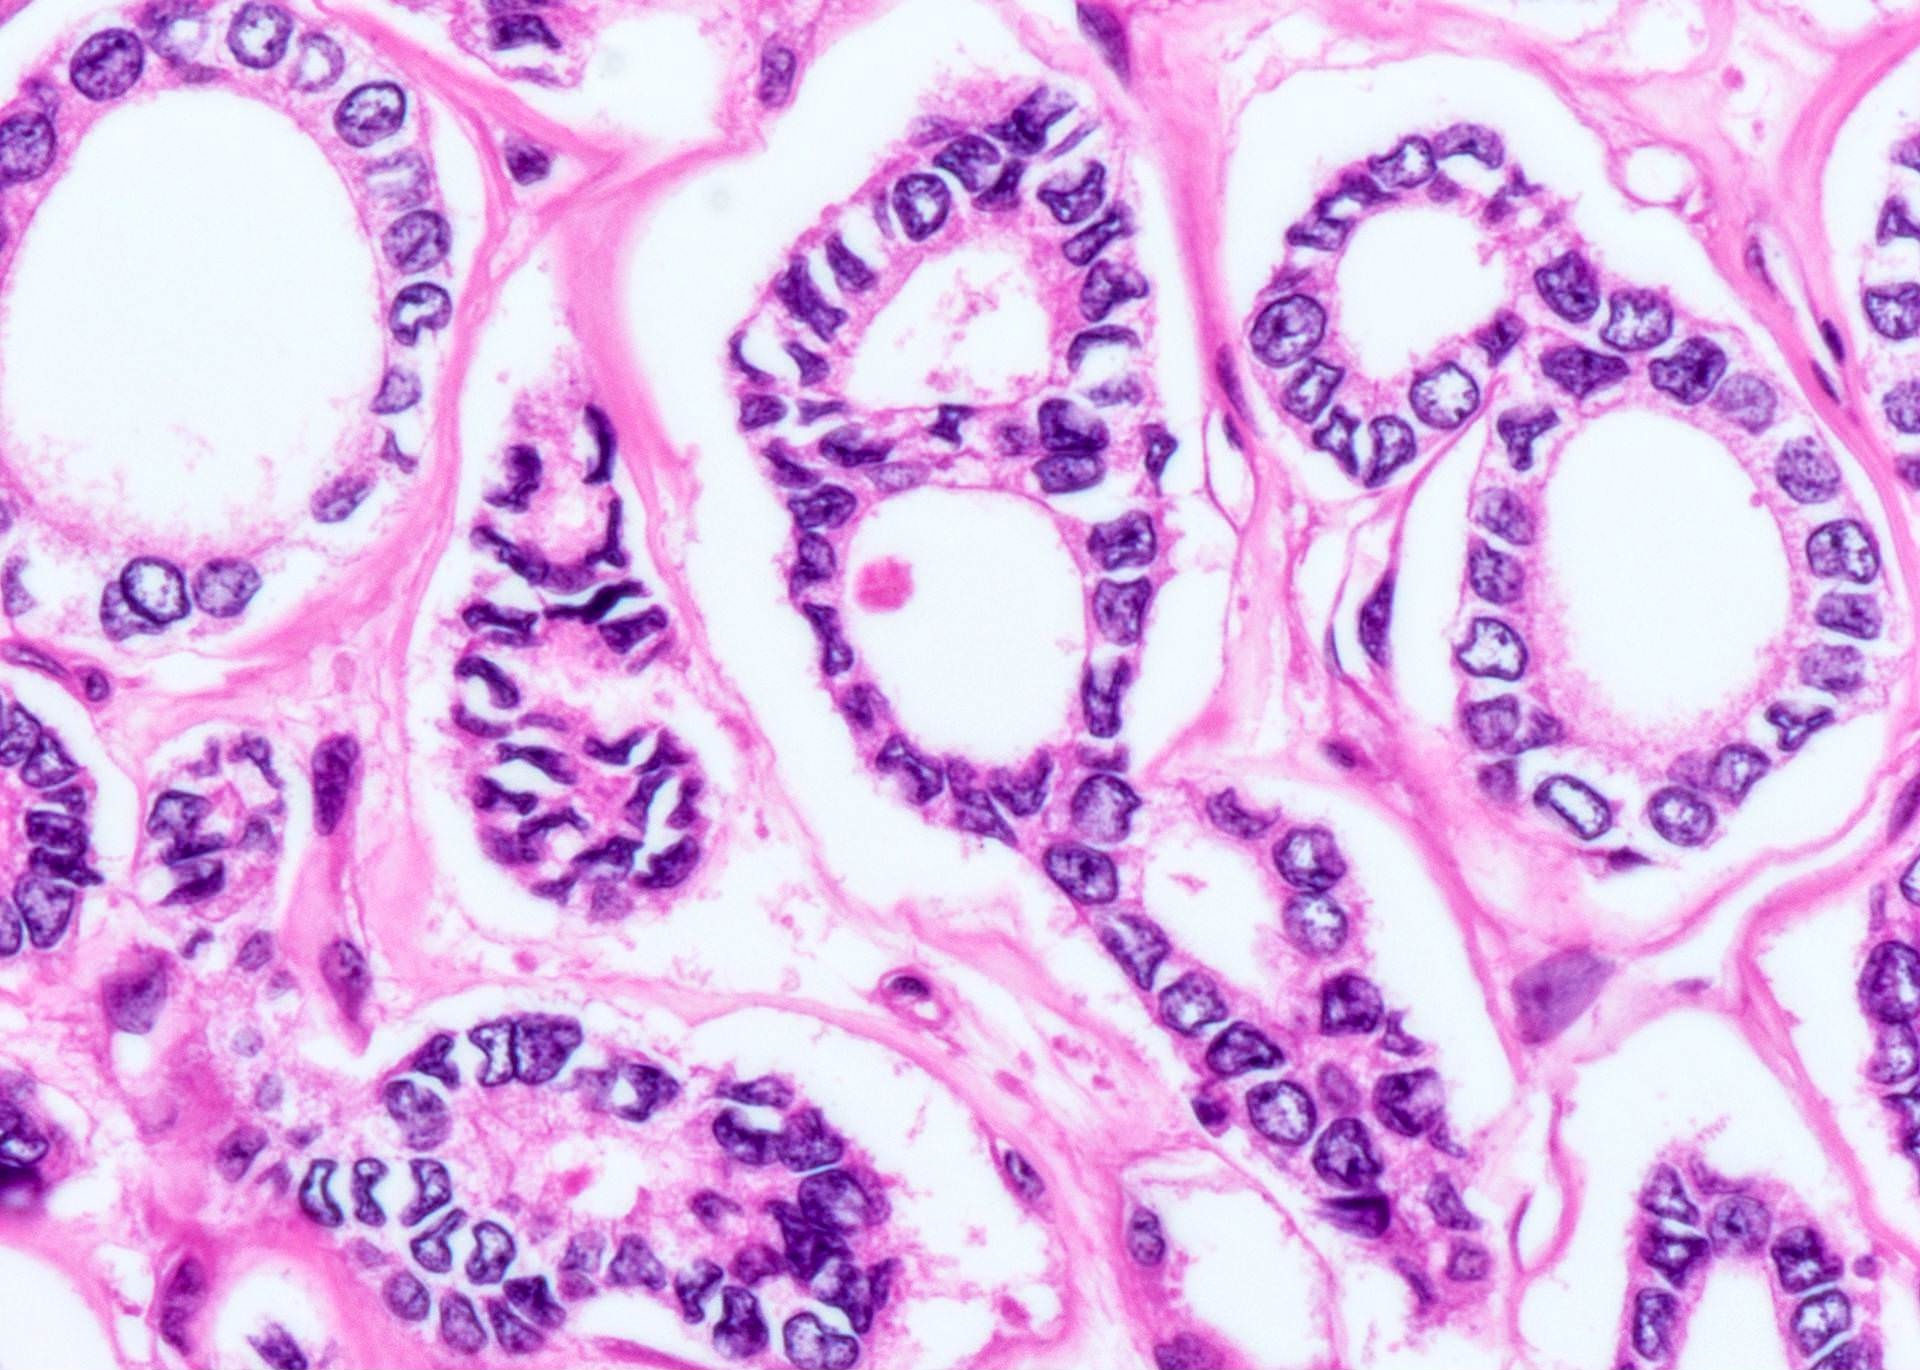

Microscopic (histologic) description

- Architecturally and cytologically different from surrounding gland

- Compression signs in surrounding thyroid tissue

- Encapsulated; thin or moderately thick capsule

- Architectural patterns (can be seen in any combination)

- Normofollicular (simple): size similar to normal thyroid follicles

- Microfollicular (fetal): smaller follicles, small amount of intraluminal colloid

- Macrofollicular (colloid): large follicles, flattened epithelium, abundant colloid

- Solid / trabecular (embryonal): minimal or no colloid

- Focal papillary pattern, occasionally; especially in hyperfunctioning adenoma and follicular adenoma with papillary hyperplasia

- Cuboidal to low columnar cells

- Small round nuclei, smooth nuclear boundary, uniformly hyperchromatic or euchromatic, dense chromatin, absent nuclear features of papillary thyroid carcinoma, nuclear score 0 or 1 (JAMA Oncol 2016;2:1023)

- Inconspicuous nucleoli

- Rarely, lipid filled vacuoles in cytoplasm

- Mitoses are uncommon

- Scant stroma

- Secondary changes: fibrosis, hyalinization, hemorrhage, hemosiderin deposition, edema, cystic degeneration, calcification, osseous or cartilaginous metaplasia

Microscopic (histologic) images

Contributed by Shipra Agarwal, M.D., Andrey Bychkov, M.D., Ph.D., Mark R. Wick, M.D., Asmaa Gaber Abdou, M.D. and AFIP

Patterns: